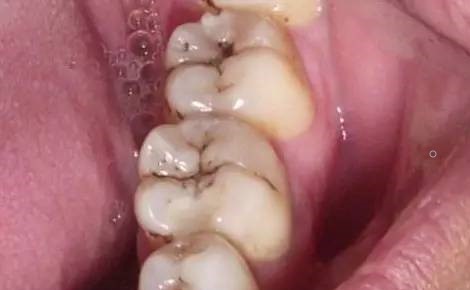

第一步浅龋。

当我们身上有小黑点时,您毫不在意地说“没事的,没感觉。”牙医说:“龋病是以细菌为主的多种因素导致的牙齿硬组织发生慢性进行性破坏的一种疾病。已经开始浅龋即牙釉质龋,需要做药物治疗或填充治疗。”